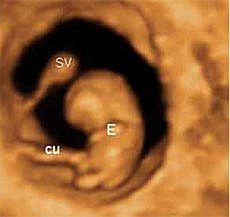

Desarrollo del feto semana 7: Brazos y piernas ya se esbozan

En la semana 7 de embarazo el embrión mide de 5 a 7 milímetros, desde el final de la cabeza (se llama vértex) hasta el final de la "cola", que será en un futuro su coxis; en la ecografía al feto se le mide desde la parte superior de su cabeza hasta la rabadilla. La cabeza aún está muy curvada sobre el pecho y crecerá mucho, ya que el cerebro se desarrolla con rapidez.